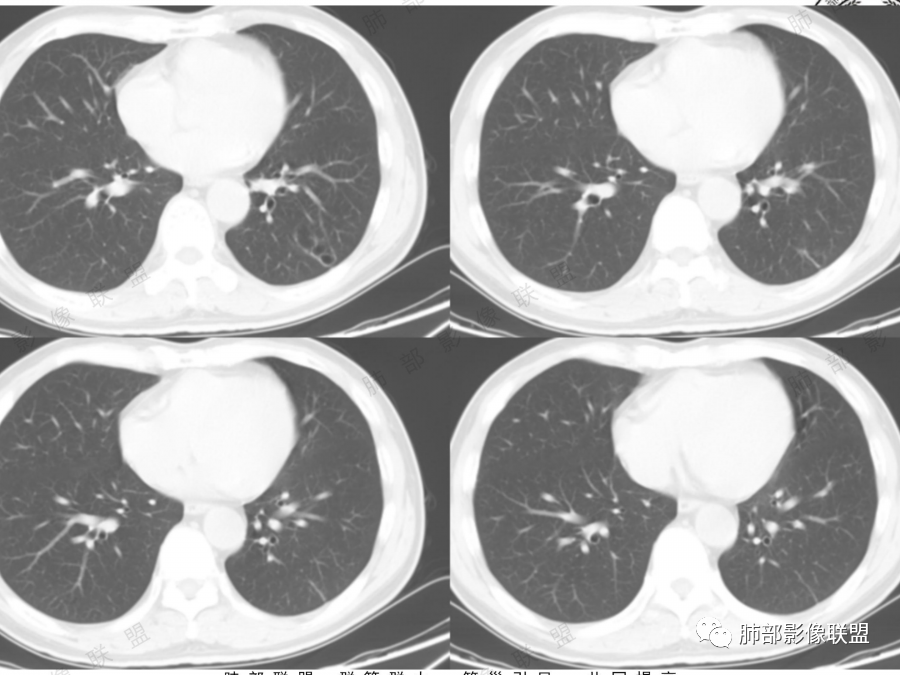

左肺下叶空腔,分隔状,壁厚薄不均,支气管截断,部分周围可见磨玻璃影,胸膜牵拉,左肺上叶多发结节,部分可见钙化,考虑1左肺下叶囊腔型腺癌。2左肺上叶结核。

中年男性,多发空腔,腔内可见分隔、壁结节。考虑:囊腔型腺癌。肺结核为陈旧性。

男51,体检发现肺部阴影,左肺下叶见多发薄壁囊腔影,可见结节,囊腔内见分隔,轻度胸膜牵拉,病灶周围少许磨玻璃影,常规考虑囊腔型腺癌,肿瘤标志物不高,除外结核。

中年男性,体检发现,吸烟史,但肺气肿背景不明显。左肺下叶囊腔病变,有一定张力,分隔明显,似有多个囊腔融合感,部分边缘见少许磨玻璃影,有支气管截断,首选囊腔型肺癌,某些先天病变(囊腺瘤样畸形等)也要考虑。

左肺上叶钙化结节,边界清楚,周围散在多发小结节,伴有磨玻璃影,考虑结核可能,左肺下叶多个囊堆积而成,大小不一,其内可见分隔,囊壁厚薄不均,病变近端与支气管相贴,支气管似扩张,考虑CCAM,鉴别囊腔性腺瘤,囊腔性腺癌

肺结核背景,左下肺簿壁囊腔,内有分格,有支气管截断,囊壁局限性增厚,嗜烟史,考虑左下囊腔型肺癌(鳞癌)。

左肺上叶陈旧肺结核,以增殖钙化灶为主,左肺上叶多发囊泡样结节,有分隔,稍分叶,周围少许磨玻璃,支气管部分截断,部分贴边穿过,老年男性,考虑囊腔型腺癌。

左肺上叶多发小结节影,部分钙化,考虑结核。左肺下叶多个囊状影,腔内见血管影,间隔稍粗大,考虑囊腔型肺癌,

老年,51岁男性病人,左上肺斑点,小结节状阴影,可见钙化,陈旧性肺结核改变,患者有长期的吸烟病史。左肺下叶背段多个囊腔肿块影,整体呈团块状类圆型,无明显壁结节,整体病灶张力较大,具备一定的膨胀感 ,支气管拉直并有突然截断改变,考虑囊腔型鳞癌。鉴别诊断:结核性病变,局限性囊性支气管扩张

男性,体检发现左肺阴影。影像表现:左上肺多发结节伴纤维条索影,部分钙化,左下肺囊腔样改变,内有分隔,部分分隔边缘见实性成分及GGO样改变,支气管从旁边经过,或受压,无明确进入依据。初步诊断:1、左上肺结核。2、左下肺囊腔型腺癌,诊断依据:分隔样囊腔,部分分隔有实变,边缘有GGO改变,鉴别诊断:1、囊腺瘤样畸形,分隔样囊腔要考虑,但部分分隔实变,部分伴GGO样改变成疑,最大的疑问是年龄51岁,体检发现,抽烟、饮酒30年,却无发病,可能性太小。2、囊腔性转移,单发分隔样囊腔转移少见,且需要病史支持。3、囊性淋巴瘤,一般以单发囊腔多见,分隔样囊腔型淋巴瘤罕见。4、感染,无相关临床症状及辅检支持,基本排除。

补充一下,虽然看到有GGO样改变,腺癌可能最大,但如果GGO是假像,有多年吸烟史,也不完全排除囊腔型鳞癌可能。

@傅昌瑜—贺州市人民医院—呼内 里面的血管进一步支持恶性。但不鉴别腺癌和鳞癌,主要鉴别的,还是多囊,张力较高,囊壁较薄(实变区除外),加GGO。